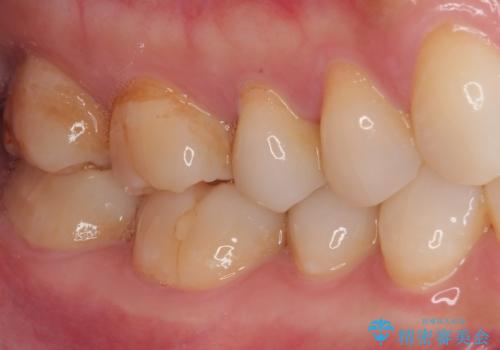

- むし歯と銀歯を気にして来院された患者様です。

銀歯の歯は既に根管治療がされており、根尖部に病変が認められないため、根管治療を行うことなくオールセラミッククラウンにて補綴治療を行うこととしました。

むし歯の症状のある歯は、ややしみることがある程度でしたが、レントゲン写真では非常にむし歯が大きく、神経組織に迫っている状態でした。

術前診査では神経を全て取る可能性は低いと予想されましたが、一部切除する可能性があることを伝えた上で治療を行うこととしました。